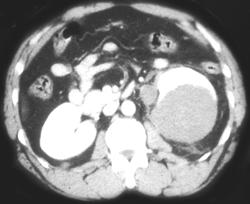

Renal Angiomyolipoma (bilateral)